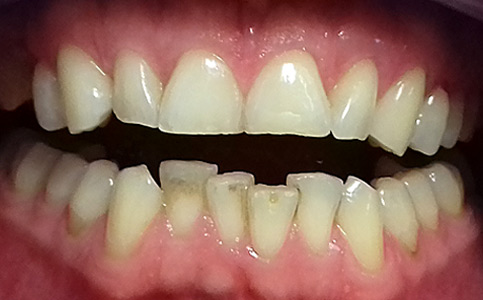

Pacjent zgłosił się z powodu niezadowalającego koloru i kształtu zębów, nie chciał także szlifować swoich zębów pod licówki/korony. Odpowiedzią na jego potrzeby był BONDING czyli estetyczna odbudowa kompozytowa. Przed wykonaniem BONDINGU pacjent był zdeprogramowany aby ustawić staw skroniowo-żuchwowy w dobrej i wygodnej pozycji, zostały odbudowane zęby tylne do kształtów anatomicznych oraz podniesienie w zgryzie aby móc estetycznie przedłużyć zęby przednie. Efekt leczenia sprawił że Pacjent opuścił nasze Centrum stomatologii i Ortodoncji z szerokim uśmiechem.